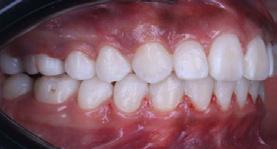

Se presenta una paciente de 20 años de edad con diagnóstico de clase II esquelética, hiperdivergente, clase I molar bilateral, relación canina clase II bilateral, mordida abierta anterior, colapso maxilar, mordida borde a borde posterior bilateral, apiñamiento moderado en superior e inferior, líneas medias desviadas. El tratamiento consistió en control del hábito, alineación, nivelación, expansión del arco superior, rotación del plano oclusal, stripping, detallado y retención. Aparatología utilizada: brackets prescripción 0 grados slot 0.018, tubos bondeables en 6’s y 7’s superiores e inferiores. Objetivos: mejorar el perfil labial, corrección de apiñamiento maxilar y mandibular, de la mordida abierta anterior y mordida borde a borde posterior bilateral, mejorar forma de arco superior, mantener clase I molar bilateral, obtener clase I canina bilateral, corrección de líneas medias dentales, relaciones esqueléticas, mantener estado periodontal, lograr correcta intercuspidación, guía de desoclusión canina, guía incisiva. Tiempo de tratamiento 6 años y 6 meses.

Caso Clínico

Una paciente de 20 años de edad se presenta con el motivo de consulta: “quiero una valoración de ortodoncia”. Estudios clínicos extraorales de inicio se observan quintos proporcionales, línea media superior desviada 1 mm a la derecha con línea media facial (Figura 1), el perfil cóncavo. Tercio inferior aumentado con respecto al tercio medio facial (Figura 2).

Estudios intraorales de inicio

En la fotografía de frente tenemos una mordida abierta anterior, mordida borde a borde posterior bilateral

Manejo de mordida abierta anterior con brackets 0 grados Figura 2. Perfil. Figura 3. Mordida cruzada anterior. Figura 4. Derecha de inicio. Figura 5. Izquierda.

Figura 6. Oclusal superior e inferior de inicio.

presencia de hábito de interposición lingual (Figura 3), clase I molar derecha (Figura 4), clase I molar izquierda ( Figura 5 ), línea media facial y dental superior coinciden, línea media facial y dental superior desviada 1 mm a la derecha apiñamiento severo en la arcada superior (Figura 6) y en la arcada inferior.